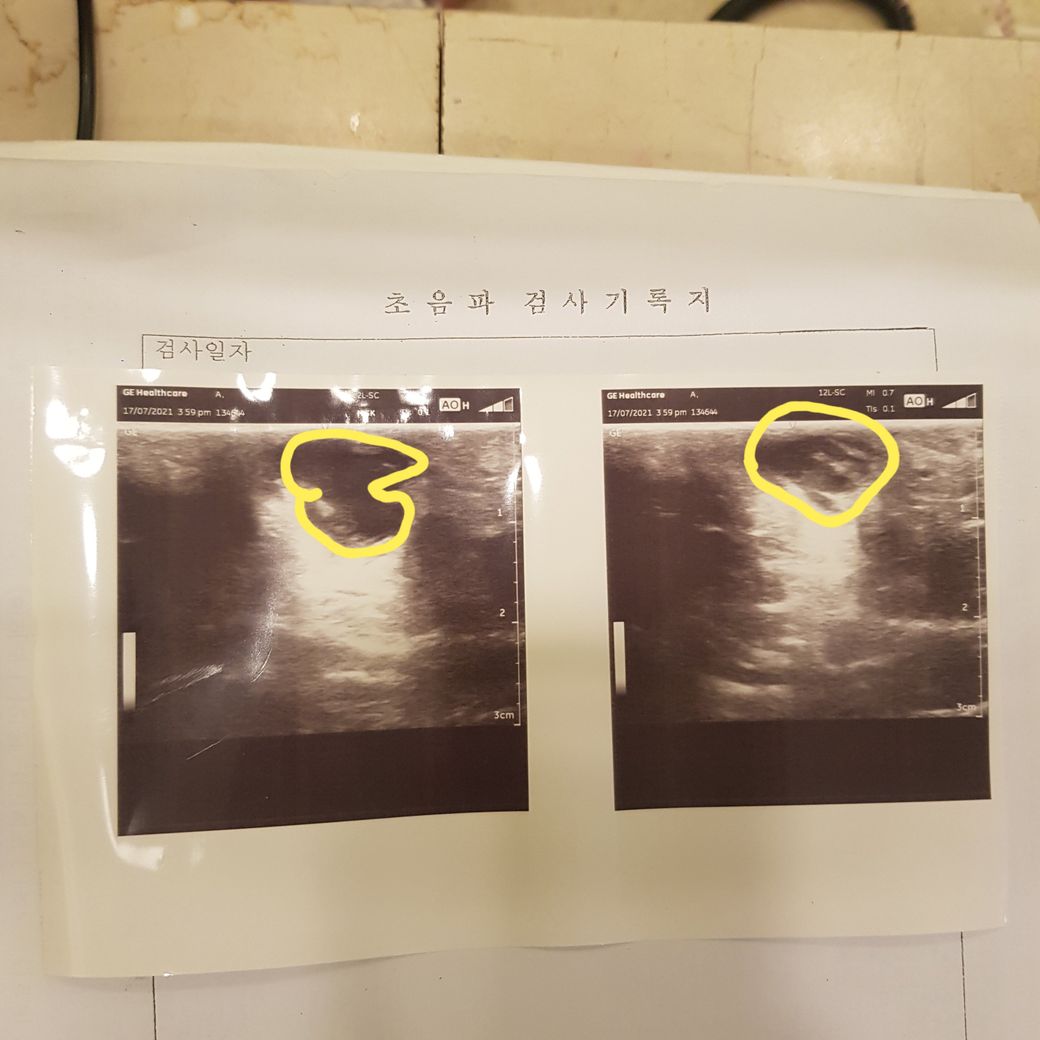

오늘 병원가서 초음파 찍어보니 종양이래요,..

크기가 밑에 초음파사진의 노란동그라미 만한 큰 종양...ㅠㅠ